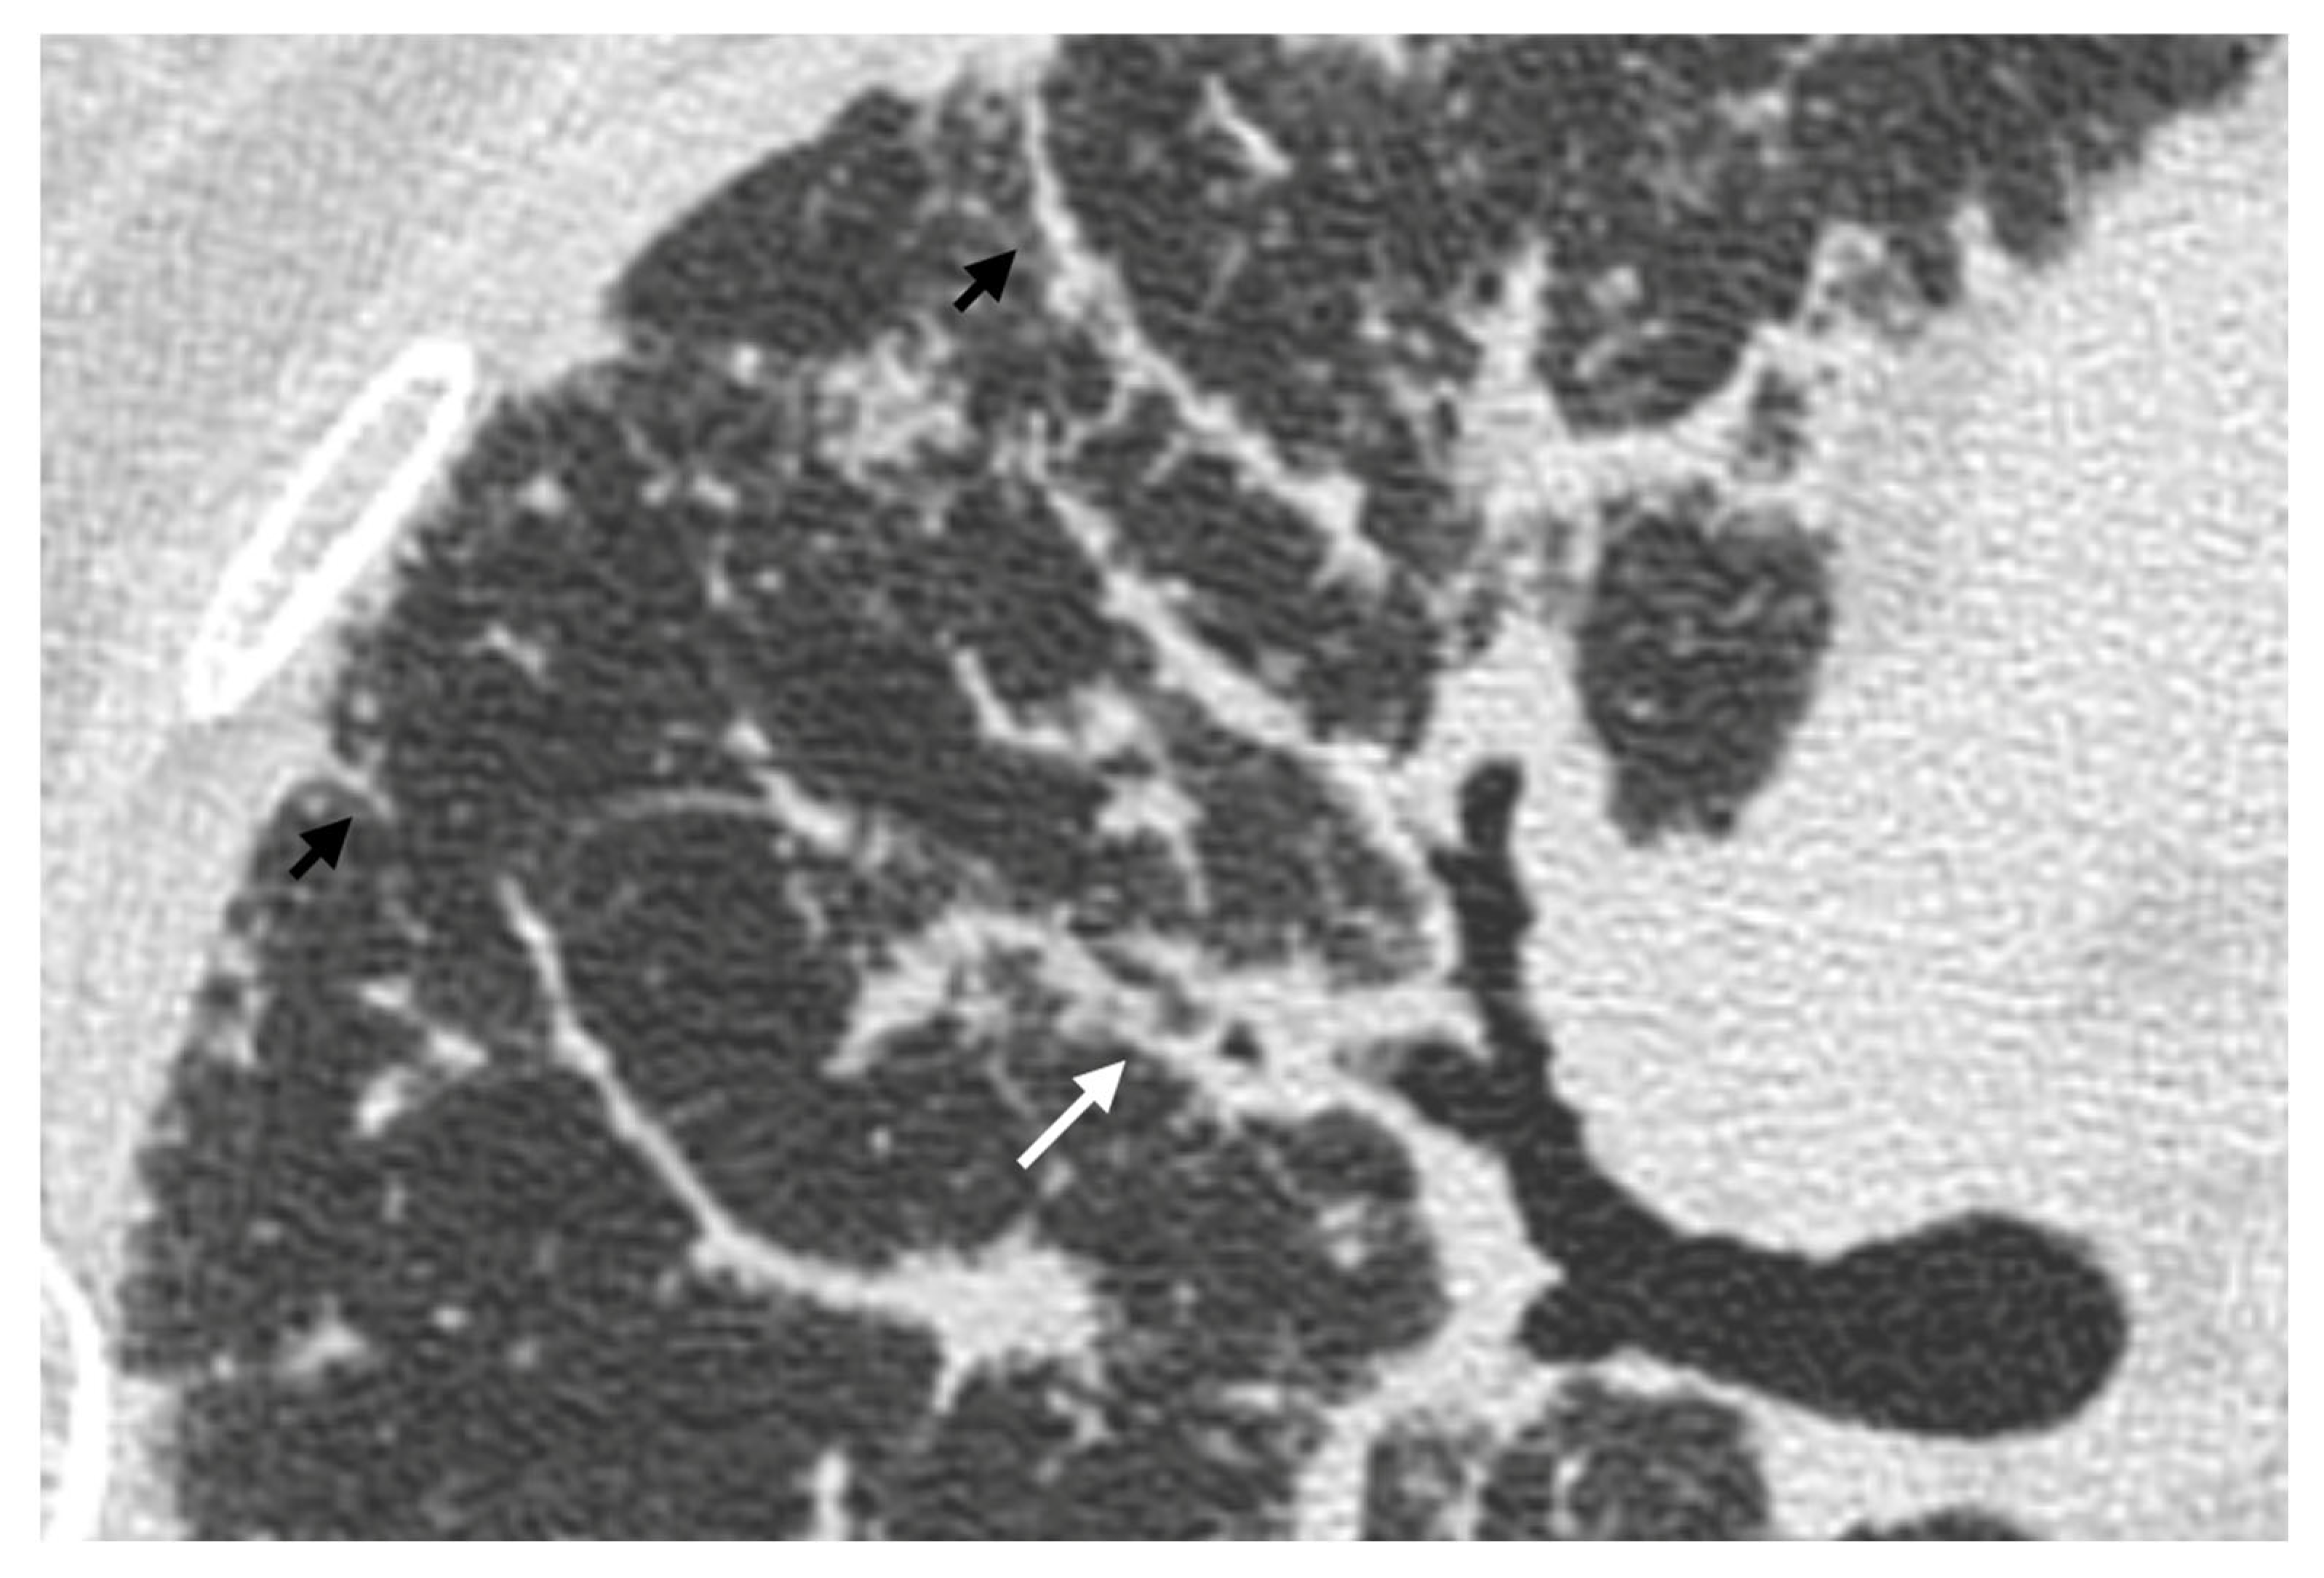

| Distribution | Perilympathic (75–90% of cases); bilateral and symmetric involvement, especially in the middle and upper lobes |

| Nodule size | Micronodules 2–4 mm in diameter |

| Morphology | Nodules with well-defined margins, round shape |

| HRCT localization | Peribronchovascular interstitium, interlobar fissures, interlobular septa |

| Evolution | Possible coalescence of micronodules into macronodules over time |